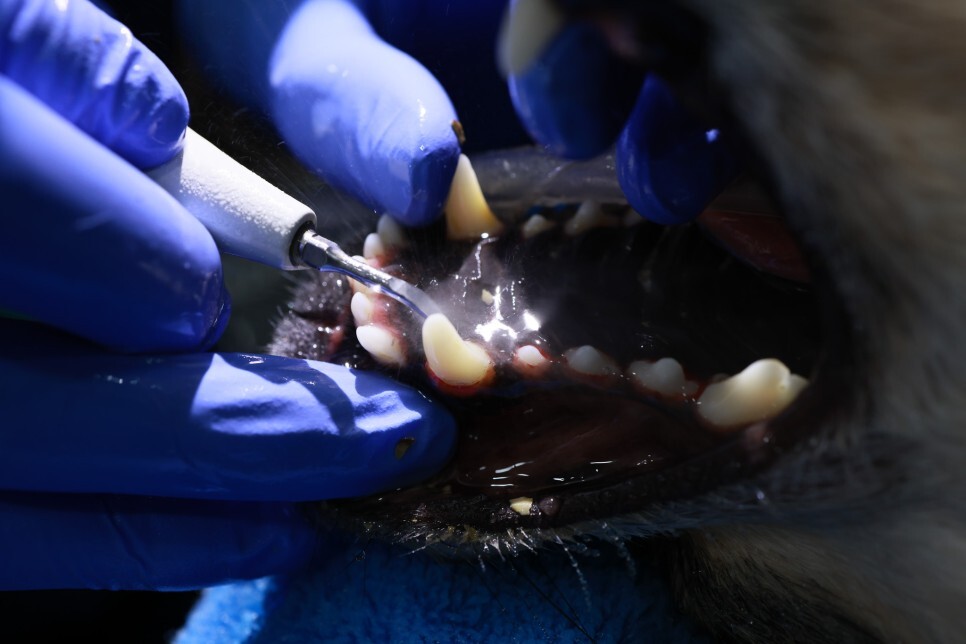

발치 중인 하원

유치가 남아 있었다고 하는데

치흡이(치아흡수질환) 의심이 조금 된다고 하는데

지금 상황에서 특별히 할 것은 없다고

애가 양치하는 것을 싫어해서..

이제라도 양치를 열심히 시켜야겠다는 다짐을..